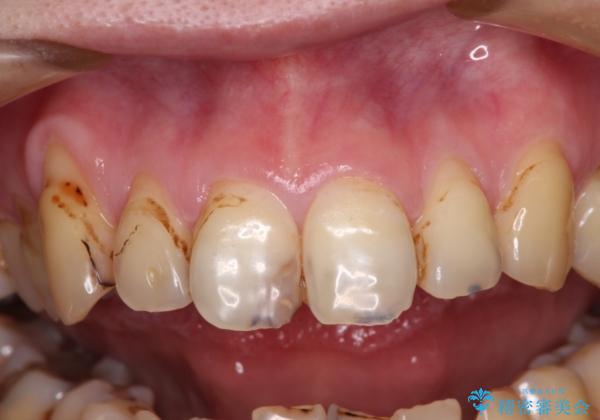

前歯は着色や虫歯治療の跡が目立っている状態で、オールセラミッククラウンによる審美治療を希望されていました。

歯肉が非常に菲薄であり、オールセラミッククラウンを装着後の近い将来歯肉退縮によりセラミックの境目が見えてくることが懸念されました。

まずは歯肉移植術により顕著に露出している歯根面を被覆して自然な歯肉ラインとし、同時に歯肉の厚みを増大させることで将来の歯肉退縮を予防することを提案しました。